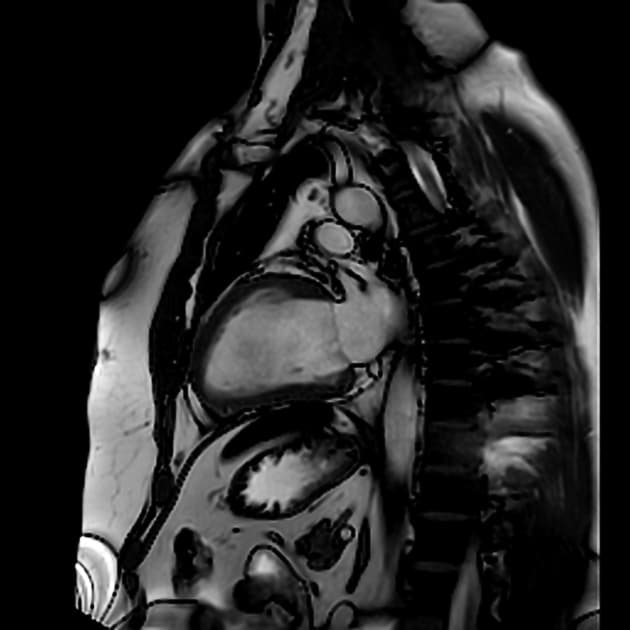

- Bệnh cơ tim phì đại dạng đỉnh thất (apical hypertrophic cardiomyopathy) với tắc nghẽn ở đoạn giữa thất (midventricular obstruction).

- Dạng bệnh cơ tim phì đại do bất thường ở sợi co cơ (sarcomeric hypertrophic cardiomyopathy) này ít gặp hơn so với dạng phì đại không đối xứng điển hình ở vùng trước vách-đỉnh (anteroseptoapical) và cũng ít gặp hơn dạng phì đại ở vùng sau vách (inferoseptal pattern).

Bệnh cơ tim phì đại dạng đỉnh thất là một thể hình thái riêng biệt của bệnh cơ tim phì đại do bất thường sợi co cơ, chủ yếu ảnh hưởng đến đỉnh thất trái. Khác với thể phì đại vách không đối xứng phổ biến hơn, thể này biểu hiện bằng sự dày lên cô lập ở vùng đỉnh, thường dẫn đến tắc nghẽn đoạn giữa thất và tạo gradient áp lực. Tình trạng căng thẳng huyết động này có thể gây thiếu máu cơ tim vùng đỉnh, hoại tử lớp dưới nội tâm mạc và xơ hóa thành thất dạng ổ, như thấy trên hình ảnh cộng hưởng từ tăng sáng muộn. Sự hiện diện của mô xơ liên quan đến nguy cơ cao hơn về rối loạn nhịp và các biến cố tim bất lợi, làm tiên lượng có thể xấu hơn. Chẩn đoán phân biệt bao gồm nhồi máu cơ tim, bệnh cơ tim do amyloid và sarcoid, nhưng hình ảnh đặc trưng dạng 'bích' trên chụp buồng thất trái và sự vắng mặt của bệnh động mạch vành giúp khẳng định chẩn đoán.